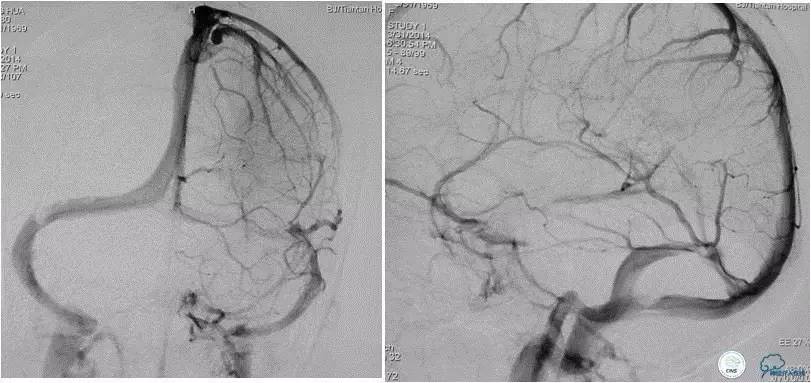

患者入院后,予以行脑动脉造影显示:右侧横窦和乙状窦交界区狭窄,左侧横窦和乙状长段重度狭窄(图3);经股静脉入路行右侧横窦和乙状窦测压显示狭窄两端压力差约为28 mmHg(图4)。遂予以阿司匹林100mg,每日一次,氯吡格雷75mg,每日一次。3d后在全麻插管下行右侧横窦-乙状窦交界处支架植入术。术中采用经右侧颈静脉入路,植入8~30mm 库克公司的ziliver支架,造影见右侧横窦-乙状窦交界处狭窄解除(图5),术中再次测压结果显示狭窄两端压力差约为1mmHg。术后自述双眼视物明显好转,但术后第3天眼底检查双视盘水肿较术前未见明显改善。

图3:脑动脉造影静脉窦期显示右侧横窦-乙状窦交界区狭窄,左侧横窦显影差,左侧半球血流大部分经右侧静脉窦途径引流。